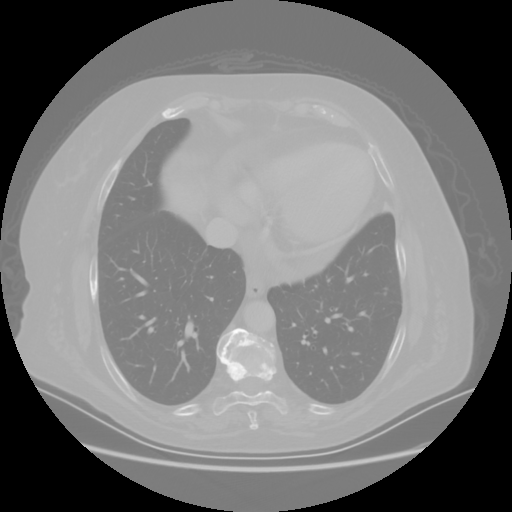

Original NATIVE CT scan (input)

No window - Raw intensity values

Lung window (WL -600, WW 1500 β†’ Low βˆ’1350, High +150)

Mediastinum window (WL 40, WW 400 β†’ Low βˆ’160, High +240)